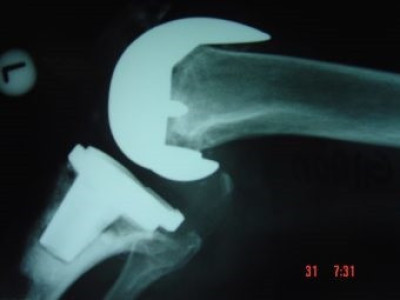

Revisión de prótesis de rodilla

Envíado por Dr. Ricardo Antonio Gómez G.